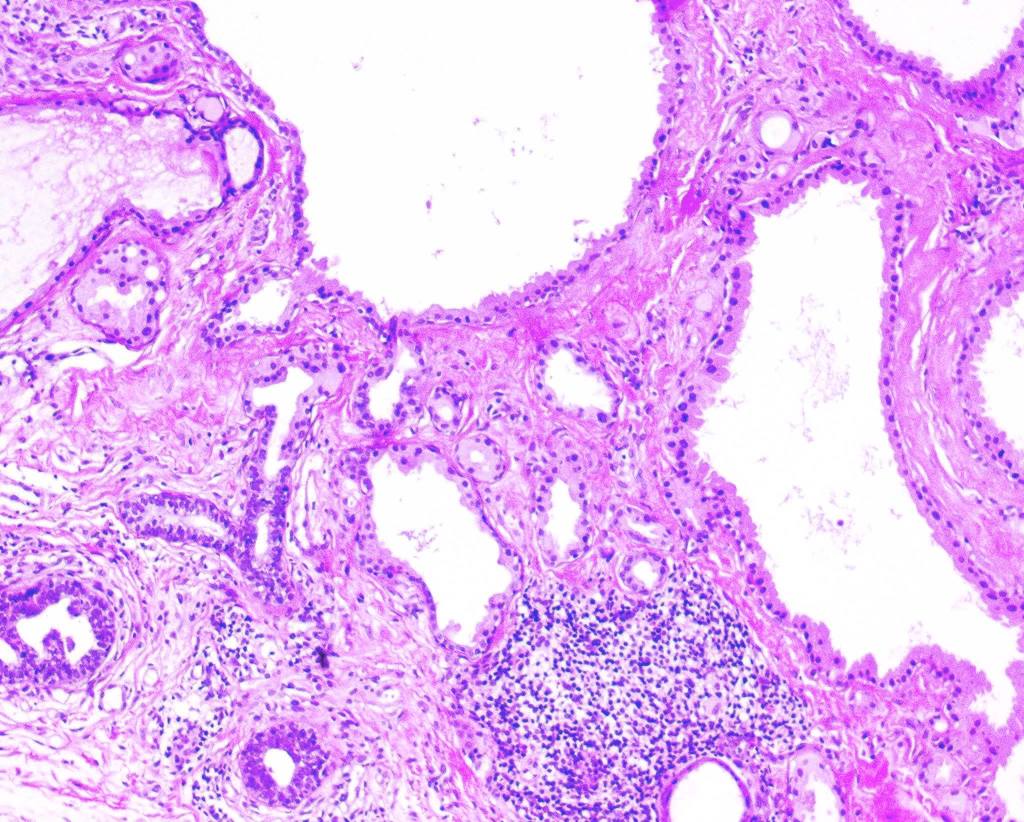

Histological features

•Pseudo-encapsulated unilocular or multilocular

•Outer myoepithelial cells & inner layer of columnar cells with eosinophilic cytoplasm showing decapitation secretion

•Adenomatous/papillary component (cystadenoma)